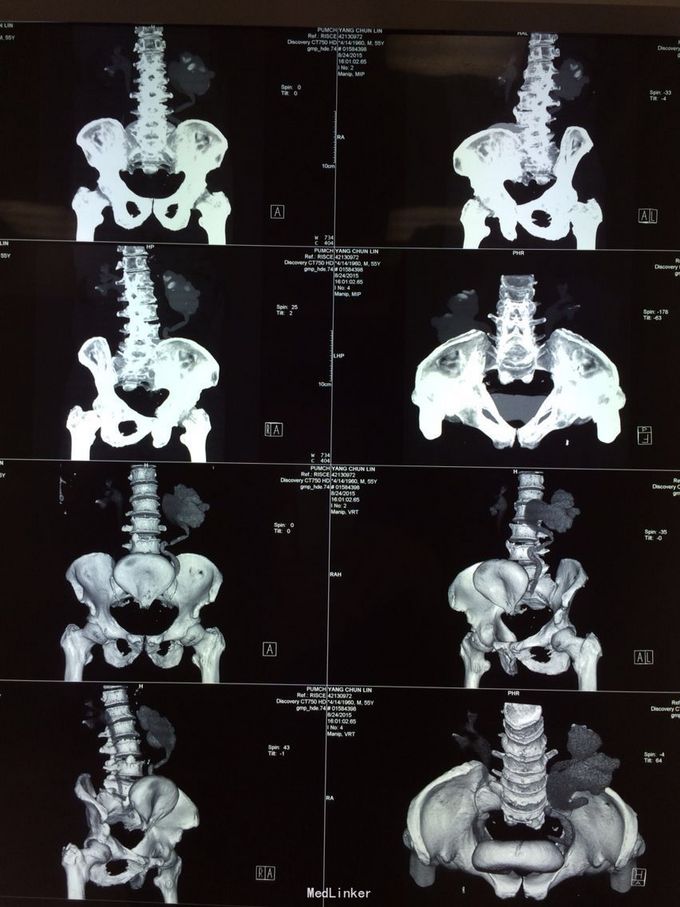

体检发现左肾积水3月余。无尿频尿急,排尿困难。当地医院彩超示:1双肾积水2右输尿管扩张3左侧输尿管走形迂曲并扩张4膀胱位置抬高5前列腺显示不清。为求进一步治疗前来我院。门诊行检查后诊断为盆腔脂肪增多症,建议患者行左肾造瘘。患者表示拒绝,至北京某医院就诊,给予行双侧输尿管D-j管置入,未成功。再次至我院就诊,门诊以“盆腔脂肪增多症”收住院。

盆腔脂肪增多症诊断目前没有统一标准,目前比较公认的是:CT,MRI发现盆腔脂肪异常增多;膀胱受压变形呈梨形、泪滴状或香蕉状;腺性膀胱炎表现;直肠-乙状结肠明显受压拉直,结肠袋消失;合并肾积水. 满足以上1或+ 2-5任意一条即可诊断;个人认为MRI提供的参考信息大于CT。输尿管D-J置入往往因输尿管受压迂曲而失败,无法缓解病情。输尿管皮肤造瘘或肾造瘘也许是这些患者的最终结局,高位的回肠代膀胱也是一种选择但存在肾积水缓解不好的风险。需要特别指出盆腔脂肪剃除不可取。长期来看输尿管膀胱再植也是无效的。